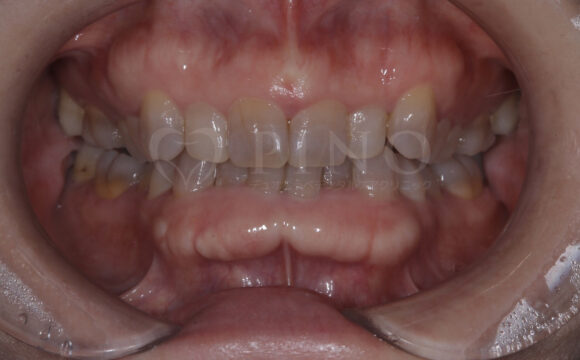

症例3:歯の黄ばみが気になる(20代女性)

主訴 歯の黄ばみが気になる 診断名 歯の内部の黄ばみ 原因 歯の内部の黄ばみ 治療期間 オフィスホワイトニング 7回 費用 ホワイトニング3ヶ月コース 116,000円 副作用・注意点 知覚過敏様症状が出る可能性がある 備考 ホームホワイトニング併用 -